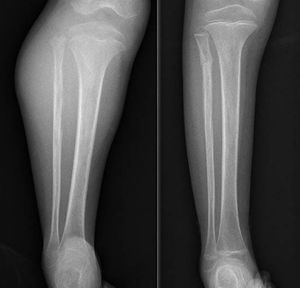

DiscusiónHemos analizado numerosos factores relacionados con el sarcoma de Ewing en una serie de 41 pacientes tratados en un mismo hospital en España durante 6 años. En nuestra serie, 2 tercios de los pacientes fueron varones y un tercio mujeres, siendo casi el 70% menores de 20 años de edad en el momento del diagnóstico anatomopatológico del tumor, datos que corresponden a lo descrito en la literatura1,4,7,8. Raramente se diagnostica en menores de 5 y en mayores de 303,13, en nuestra serie encontramos cinco casos (12,2%) en ese rango de edad: un paciente de 51 años y otro de 49 años de edad con formas extraesqueléticas (muslo –figura 3– y pierna respectivamente) y otros tres pacientes de 31, 32 y 35 años de edad con Ewing óseos en tibia y fémures respectivamente (fig. 4).

En lo que a localización se refiere, las diáfisis o segmentos metafisodiafisarios de huesos largos, especialmente fémur, constituyen la localización más frecuente de asiento de este sarcoma, en nuestra serie casi la mitad del total de tumores asentaban en dicha localización (18 casos) siendo el fémur el hueso más frecuente, seguido de peroné, tibia y húmero. Los huesos planos se ven afectados con mayor frecuencia que en otros sarcomas óseos en esta enfermedad, un cuarto de nuestros pacientes presentaba asiento en esqueleto axial, 3 en pelvis y 8 en columna vertebral, constituyendo el sacro la sublocalización más común de este grupo. Hasta un 20% son sarcomas extraesqueléticos, tumores de partes blandas sin afectación ósea pero con la misma histología que el Ewing óseo, asentando sobre todo a nivel paravertebral, pared torácica y en miembros inferiores. Nuestro análisis encontró un 21,95% de casos extraesqueléticos los cuales se distribuyeron en miembros inferiores la mayoría y a nivel paravertebral y epidural (2 casos). No encontramos ningún caso de localización epifisaria y solo uno de los pacientes debutó con una fractura patológica, datos que concuerdan con la literatura actual.